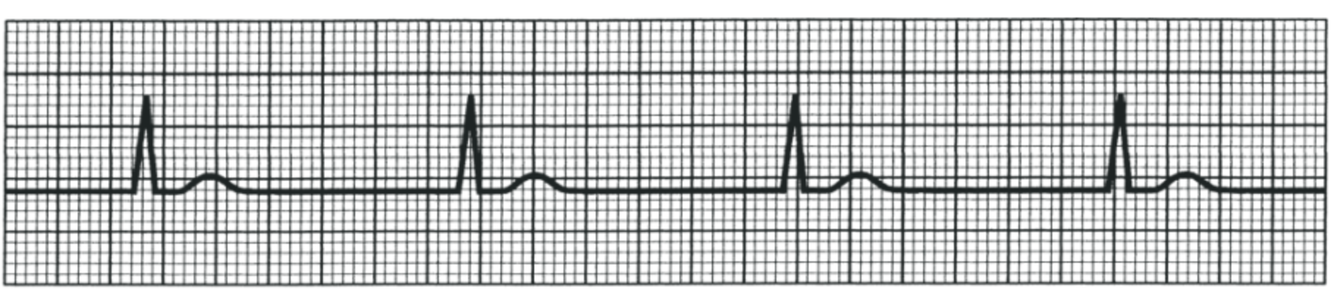

What is this?

First degree AV Block